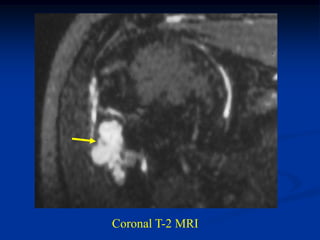

Case #120

38 year female

enchondroma

distal femur

Coronal T-2 MRI

tumor